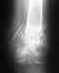

| Описание МРТ |  |  Последствия травмы: Отправитель: Владимир 16 Февраль 2019, 17:55

Травма произошла когда я шел по улице, правая нога подскользнулась на льду и поехала в сторону. На левой(осталась на месте) присел на корточки и ощутил в ней боль в области колена.Подскажите насколько тяжелая травма и сколько времени нельзя давать нагрузку на ногу